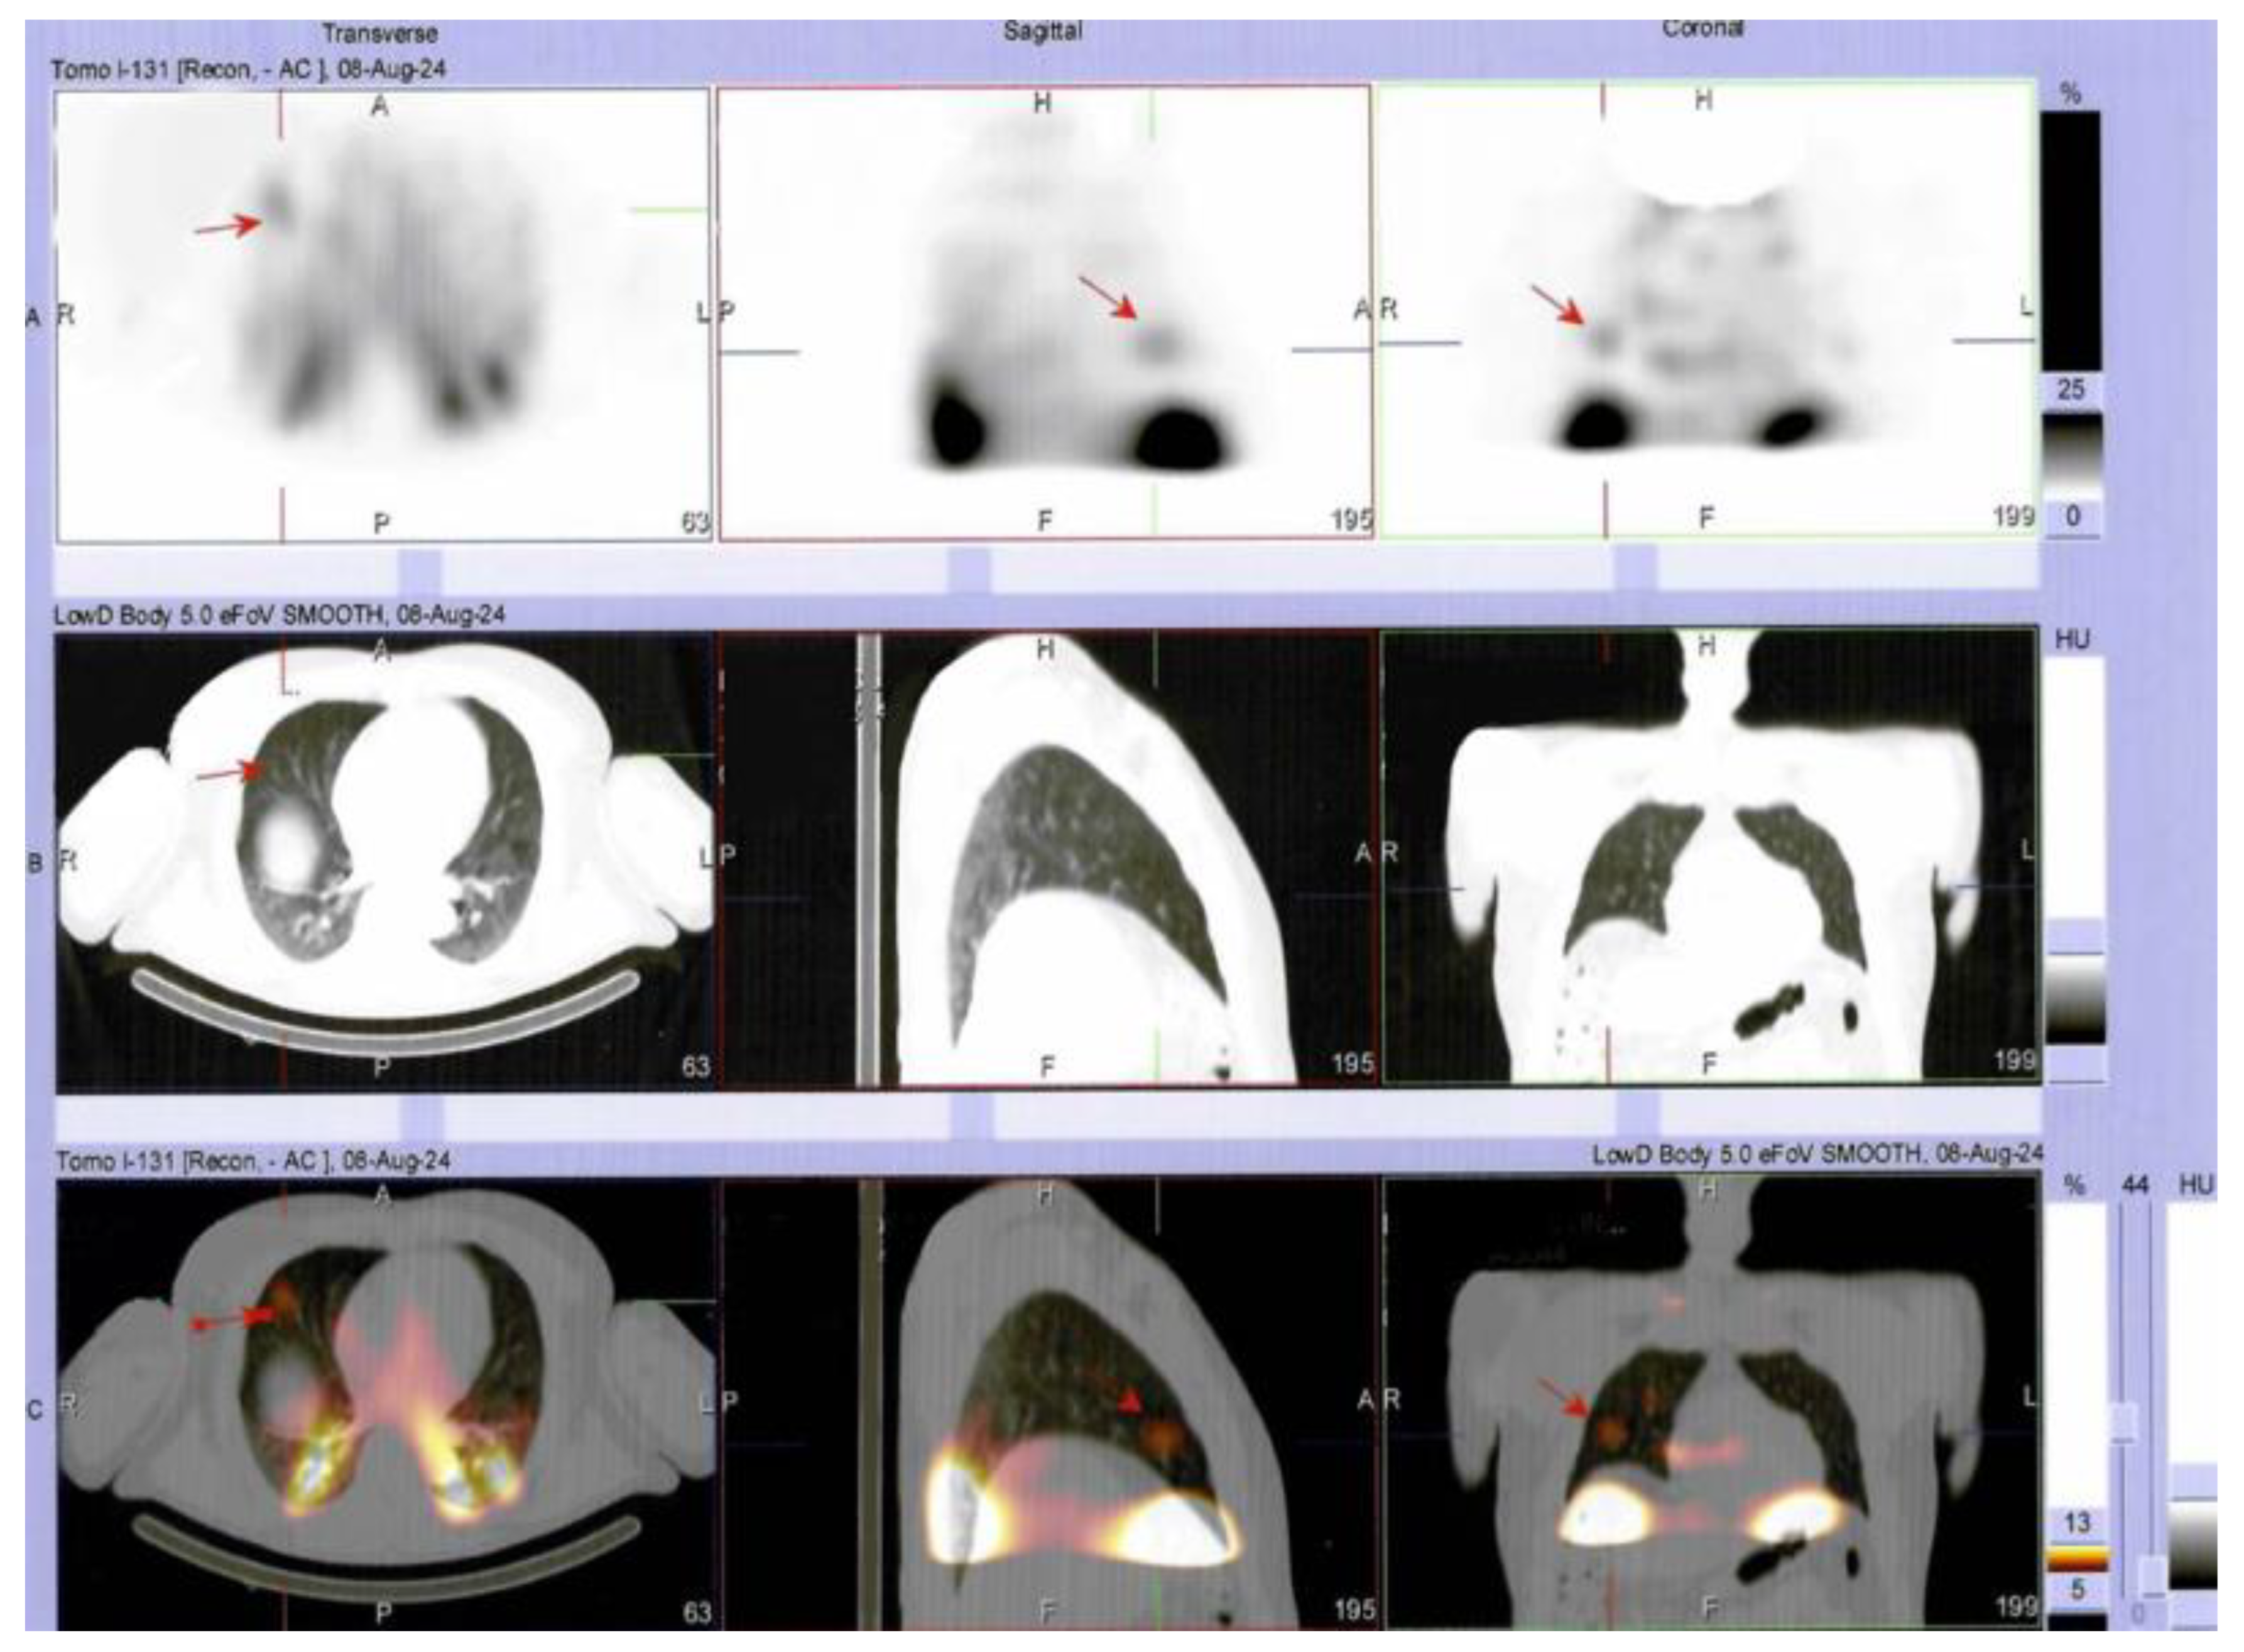

Multilayered Insights into Poorly Differentiated, BRAFV600E-Positive, Thyroid Carcinoma in a Rapidly Developing Goiter with Retrosternal Extension: From En “Y” Cervicotomy to SPECT/CT-Positive Lung Metastases

Sima, O.-C.; Cucu, A.-P.; Terzea, D.; Nistor, C.; Vasilescu, F.; Eftimie, L.-G.; Ciobica, M.-L.; Costachescu, M.; Carsote, M. Multilayered Insights into Poorly Differentiated, BRAFV600E-Positive, Thyroid Carcinoma in a Rapidly Developing Goiter with Retrosternal Extension: From En “Y” Cervicotomy to SPECT/CT-Positive Lung Metastases. Diagnostics 2025, 15, 2049. https://doi.org/10.3390/diagnostics15162049

Sima O-C, Cucu A-P, Terzea D, Nistor C, Vasilescu F, Eftimie L-G, Ciobica M-L, Costachescu M, Carsote M. Multilayered Insights into Poorly Differentiated, BRAFV600E-Positive, Thyroid Carcinoma in a Rapidly Developing Goiter with Retrosternal Extension: From En “Y” Cervicotomy to SPECT/CT-Positive Lung Metastases. Diagnostics. 2025; 15(16):2049. https://doi.org/10.3390/diagnostics15162049

Chicago/Turabian StyleSima, Oana-Claudia, Anca-Pati Cucu, Dana Terzea, Claudiu Nistor, Florina Vasilescu, Lucian-George Eftimie, Mihai-Lucian Ciobica, Mihai Costachescu, and Mara Carsote. 2025. "Multilayered Insights into Poorly Differentiated, BRAFV600E-Positive, Thyroid Carcinoma in a Rapidly Developing Goiter with Retrosternal Extension: From En “Y” Cervicotomy to SPECT/CT-Positive Lung Metastases" Diagnostics 15, no. 16: 2049. https://doi.org/10.3390/diagnostics15162049